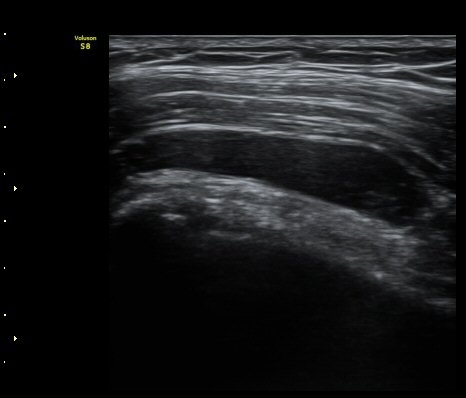

°üÀý³» ¼ö¾×Àú·ù´Â ¶Ñ·ÈÇÏÁö ¾Ê´Ù(±×¸² 3). ±Ø»ó°Ç Á¾´Ü¸é°Ë»ç¿¡¼­ Á¡¾×³¶³» ¼ö¾×

Àú·ù°¡ °üÂûµÈ´Ù(±×¸² 4, 5). ±Ø»ó°Ç Ⱦ´Ü¸é À­ ºÎºÐ¿¡¼­ °æ¹ÌÇÑ ¼ö¾×Àú·ù¸¦ º¸ÀδÙ(±×¸² 6).